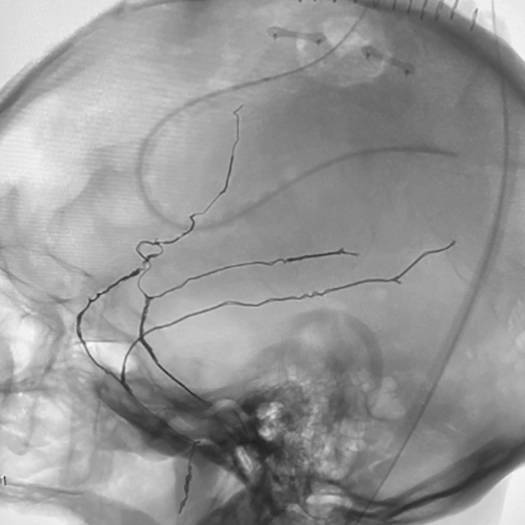

angiogram of embolization coils in a vessel

MMA embolization with 3 SwiftPAC coils: 45 cm, 15 cm, 30 cm

MMA Embolization

• SwiftPAC coils offered embolization

• MIDWAY 43 provided delivery support

• BENCHMARK071 provided stable, reliable access

• A combo designed to support confident, controlled delivery (see case to left)